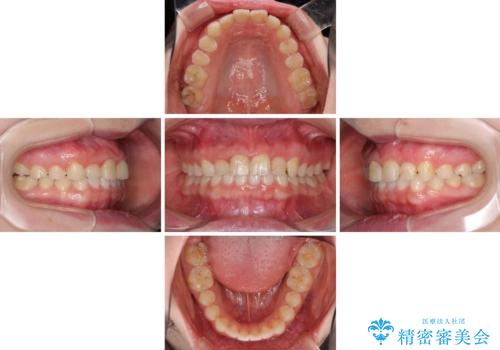

- 2年6ヶ月

上下前歯の歯列不正はインビザラインにより歯列を整え、その後に、前歯5本をオールセラミッククラウンにて補綴治療することとしました。

矯正治療にて歯並びを整えた後に、虫歯の大きかった5本の歯をセラミッククラウンにて補綴し、明るい口元になりました。